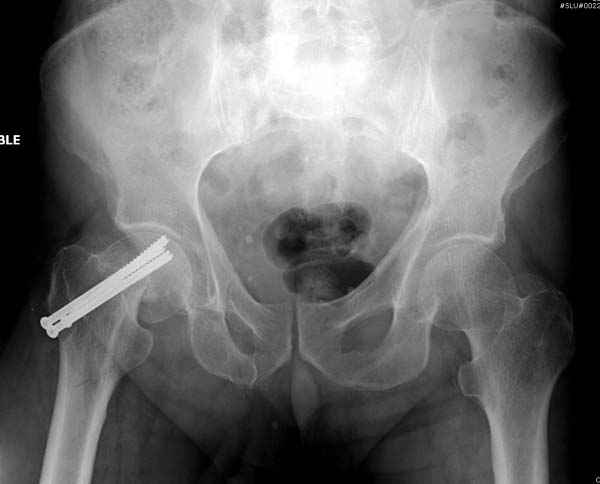

На второй день после выписки упал дома. Снимки приложены. Коллеги рекомендуют удаление шурупа и вытяжение. Что делать?

Привет из солнечного Будапешта с Eurotrauma-2008. Да, замечательный пример. Получается, профилактику расхождения отломков шейки надо было проводить каким-то реконструкционным или проксимальным гвоздем, причем сразу длинной версией. Сейчас, наверно, так и надо бы сделать.

Правильно, ситуация изменилась, как говорят у нас теперь "different animal", надо решать проблему подвертельного перелома. При наличии различных вариантов фиксаторов, включая Страйкер Гамма 3, мы выбрали DePuy Antegrade Trachanteric Nail из-за многовариантности проксимальной фиксации и двойного изгиба. Вводится через вертел под 8 градусным углом, и есть достаточный передний диафизарный изгиб, предупреждающий пенетрацию дистального переднего кортекса.

Но ведь и головка бедра сползла в варус - отчего ограничились только фиксацией подвертельного перелома, а не убрали винты и не сделали репозицию шейки?